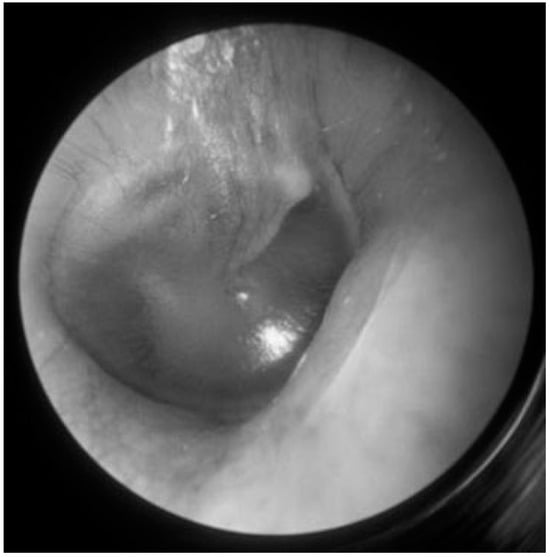

A 19-year-old man was presented with a 5-year history of right-sided otalgia and tinnitus. The pain was deep and penetrating in character, intermittent, and lasted for 4 to 5 h, radiating to the right mastoid region. Tinnitus was in the form of whistle and also intermittent with the same duration as otalgia. The patient reported the right-sided nasal obstruction only during the attacks of otalgia and tinnitus. He had no history of head trauma and surgery and he was treated for migraine and otitis media without success. The otoendoscopic examination revealed normal right-sided external auditory canal and tympanic membrane (Figure 1) and the audiological evaluation showed a normal hearing. During rhinoscopic and nasal endoscopic examination, there was no sign of inflammation. The author found a normal nasal mucosa with a mucosal contact between the large, right-sided septal spur and lateral nasal wall, which was confirmed by computed tomographic (CT) scan of the paranasal sinuses (Figure 2a,b). During an otalgia attack, the author placed a small 5% lidocaine and epinephrine-soaked cotton pledget on the contact point and, after 15 min, the patient experienced a significant reduction in intensity of earache and tinnitus. The patient underwent a septoplasty under general anesthesia. A few days postoperatively, the patient was free of otalgia, with significant improvement in tinnitus intensity, and without the right-sided nasal discharge. At 12 months follow-up, the patient reported no further otalgia and tinnitus.

Figure 1.

The otoendoscopic finding revealed a normal right tympanic membrane.